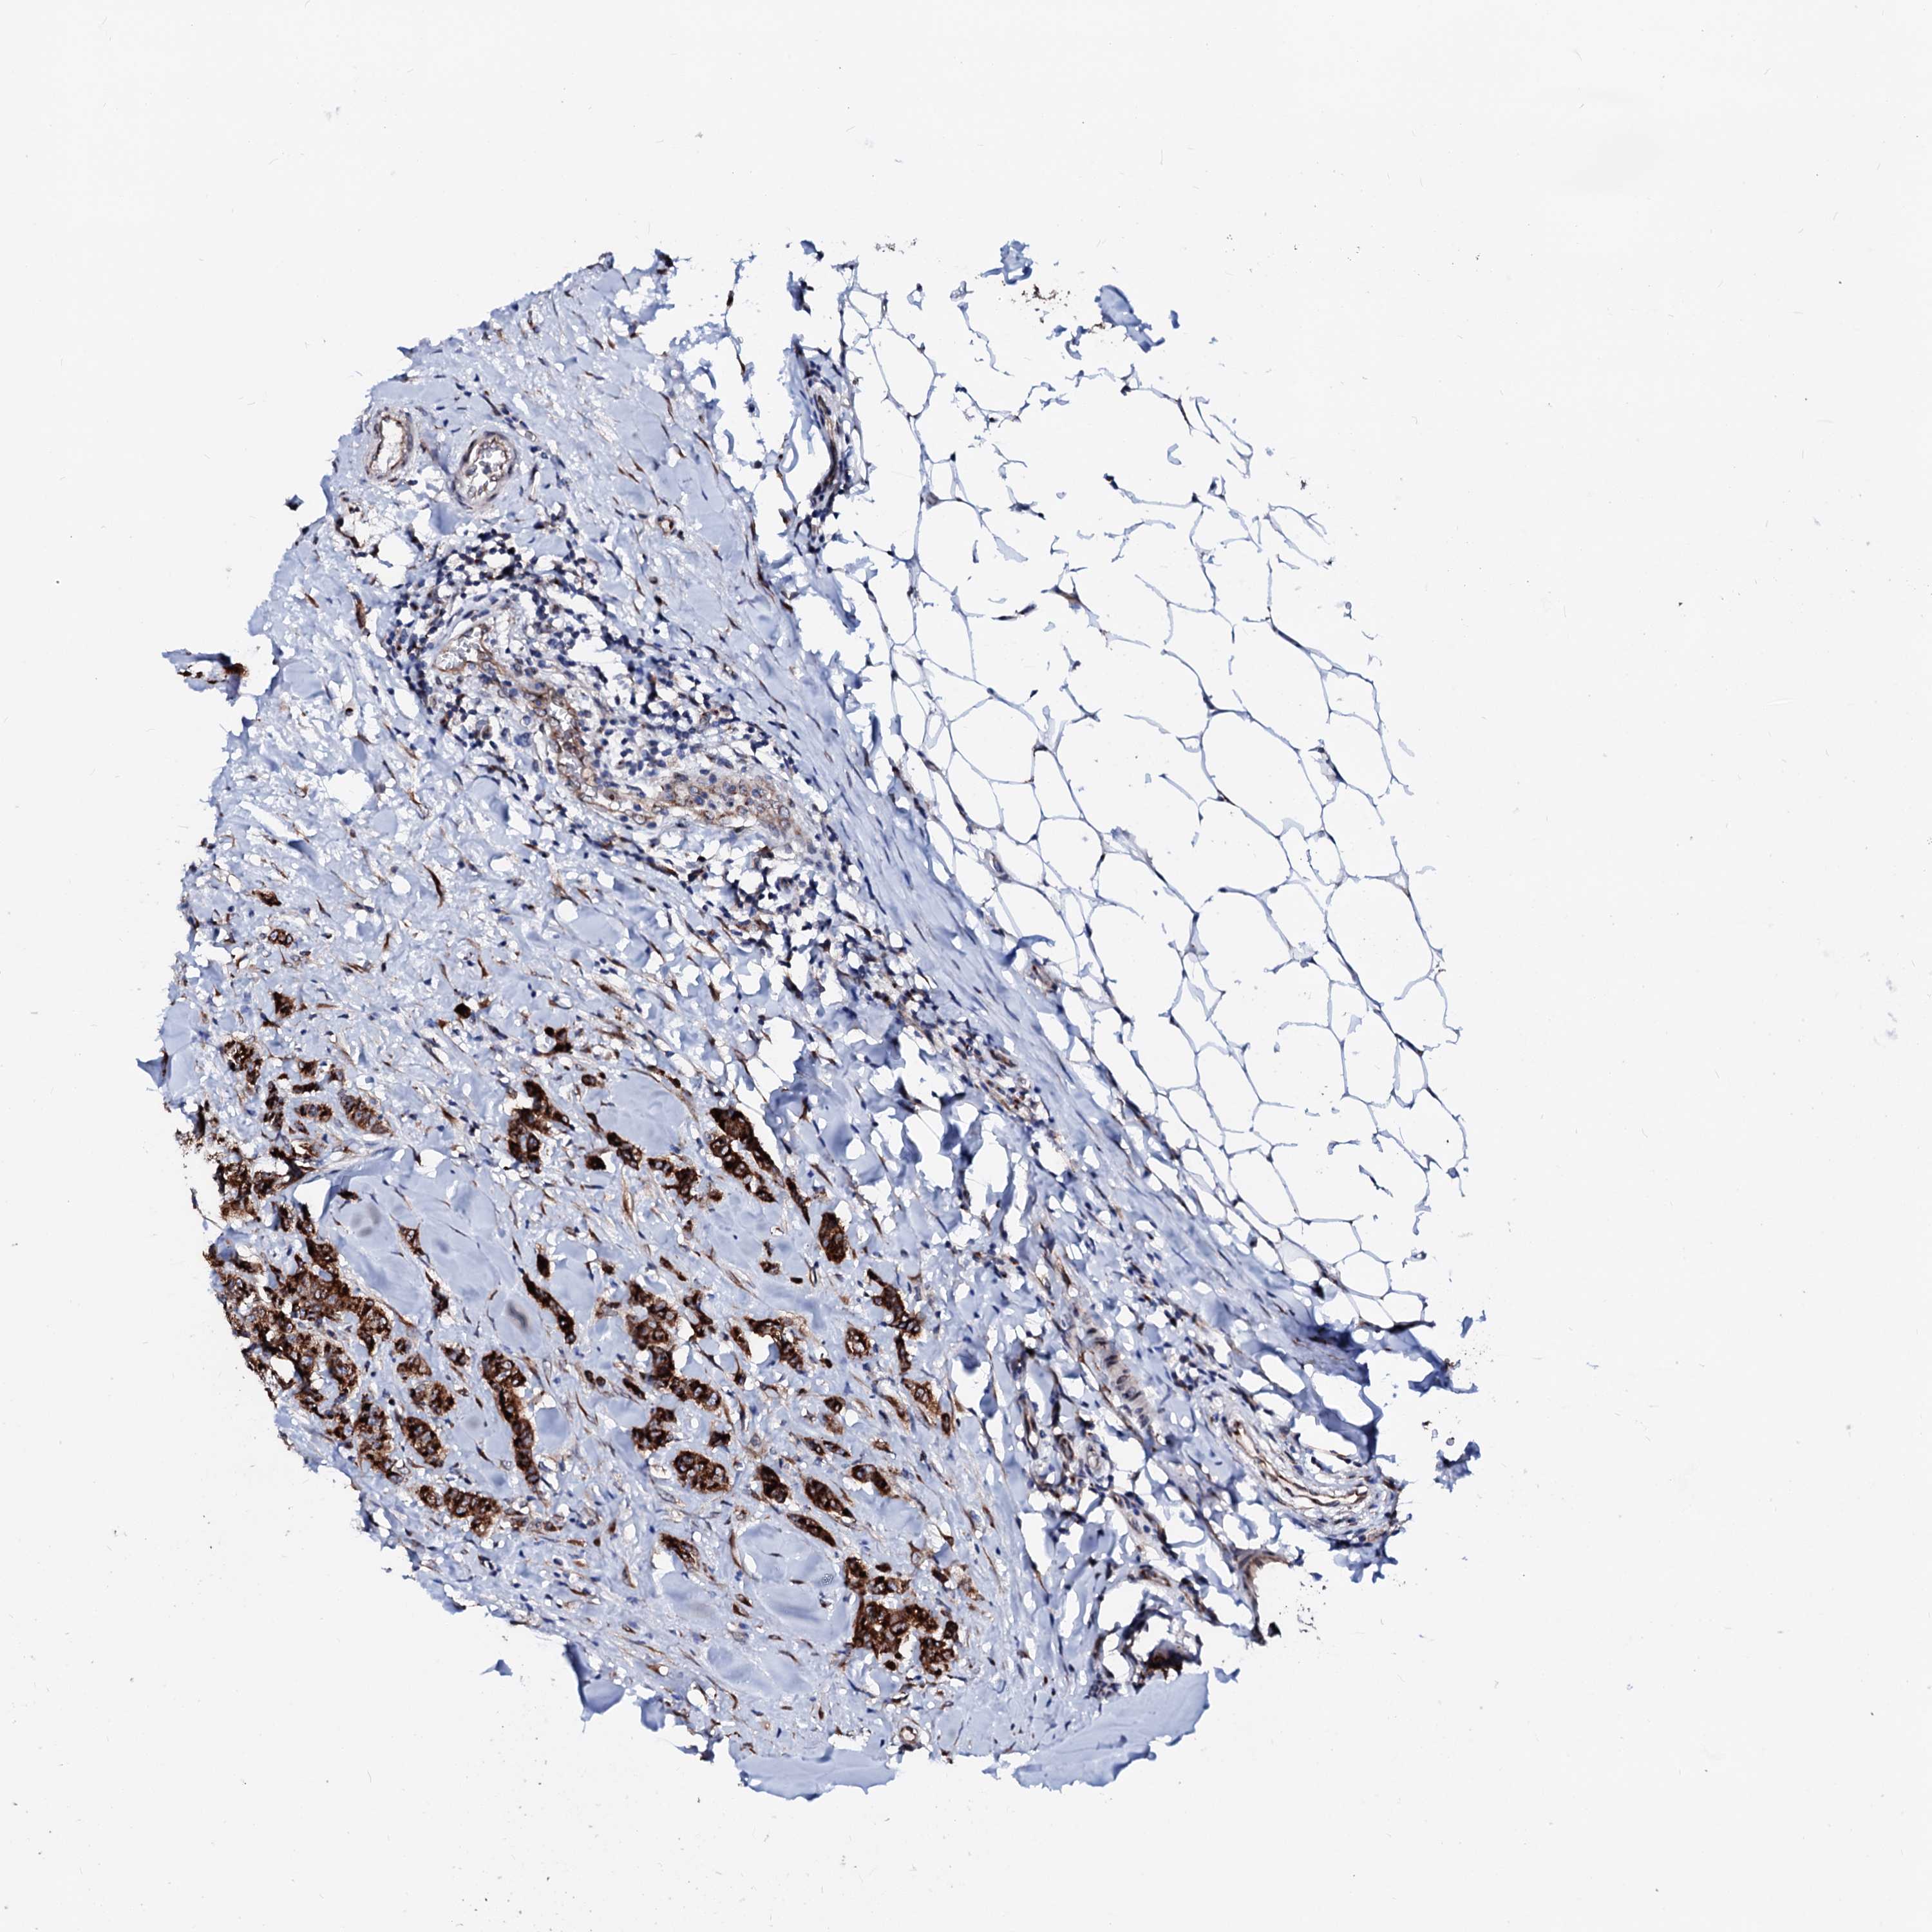

BRCA TCGA BRCA VALIDATION PROTEIN EXPRESSION

ANTIBODIES

AND

VALIDATION